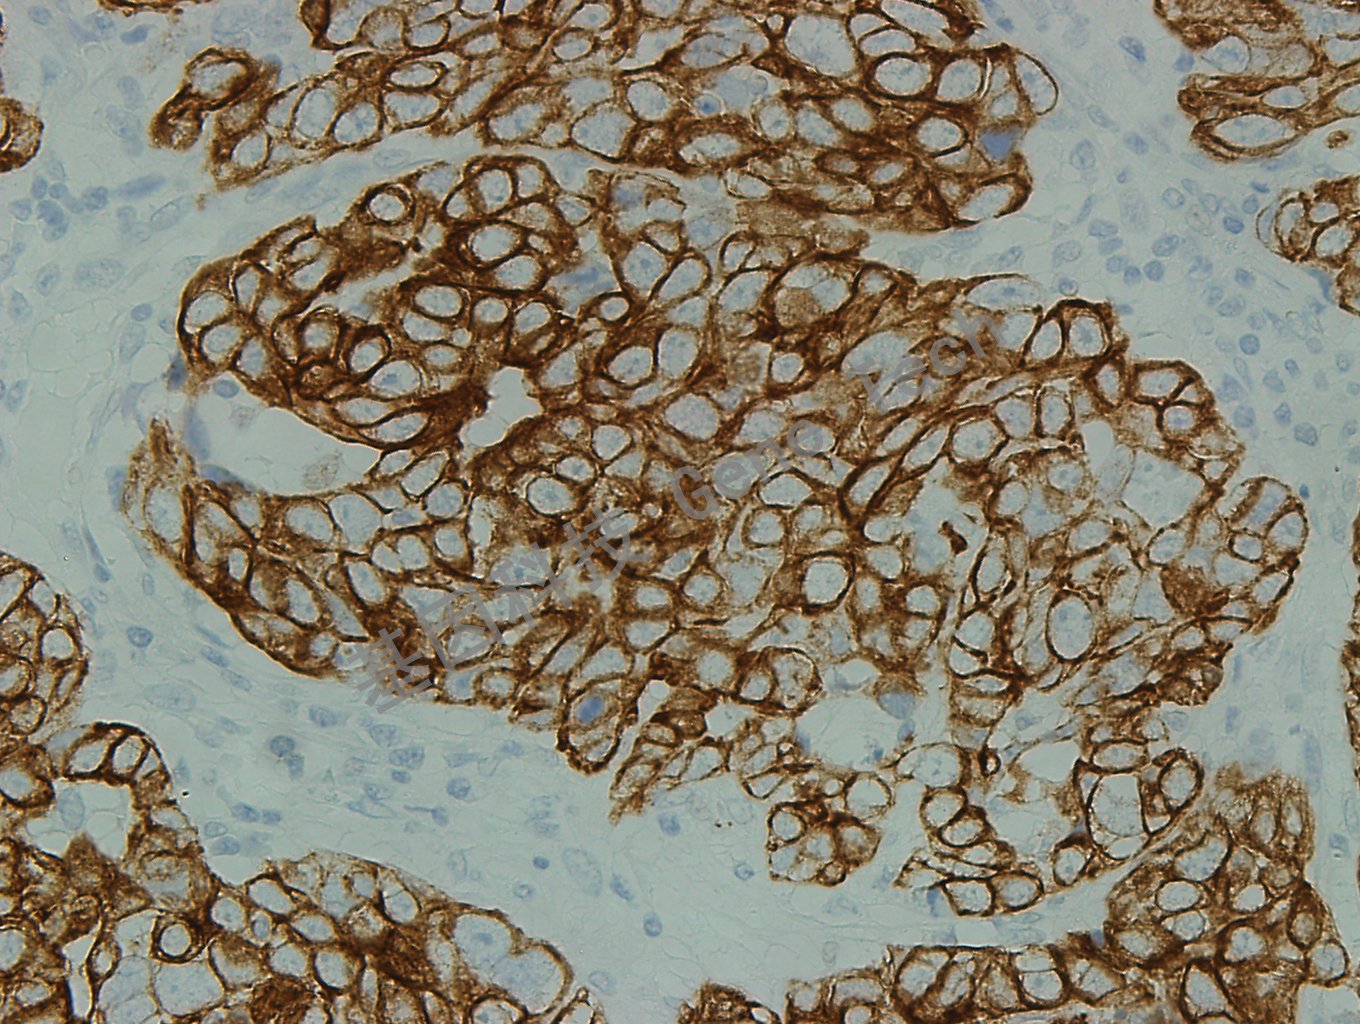

乳腺癌石蜡切片,用CK7(GT2446)染色,细胞浆阳性,DAB 显色。

乳腺癌石蜡切片,用CK7(GT2446)染色,细胞浆阳性,DAB 显色。(40×)